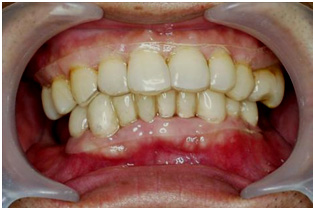

四、相關治療圖片

| 提升病患放射線治療後之口腔健康,降低放射線後猛爆性齲齒及放射性骨壞死的發生機率 |